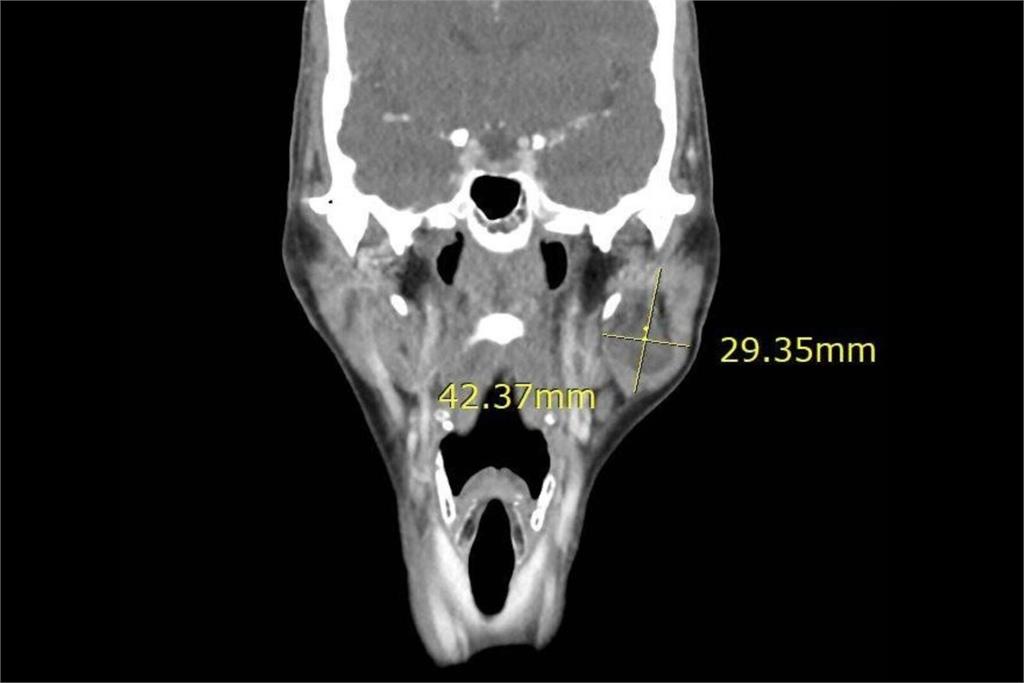

近日一名國中生因固定位置腹痛且走路彎腰就診,經超音波檢查發現闌尾發炎,轉院後電腦斷層確診為闌尾炎,緊急手術後順利康復。該案例顯示及時就醫的重要性。